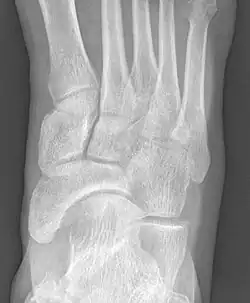

![]() X-ray of the foot showing an accessory navicular bone | |

An accessory navicular bone is an accessory bone of the foot that occasionally develops abnormally in front of the ankle towards the inside of the foot. This bone may be present in approximately 2-14% of the general population and is usually asymptomatic.[1][2][3] When it is symptomatic, surgery may be necessary.